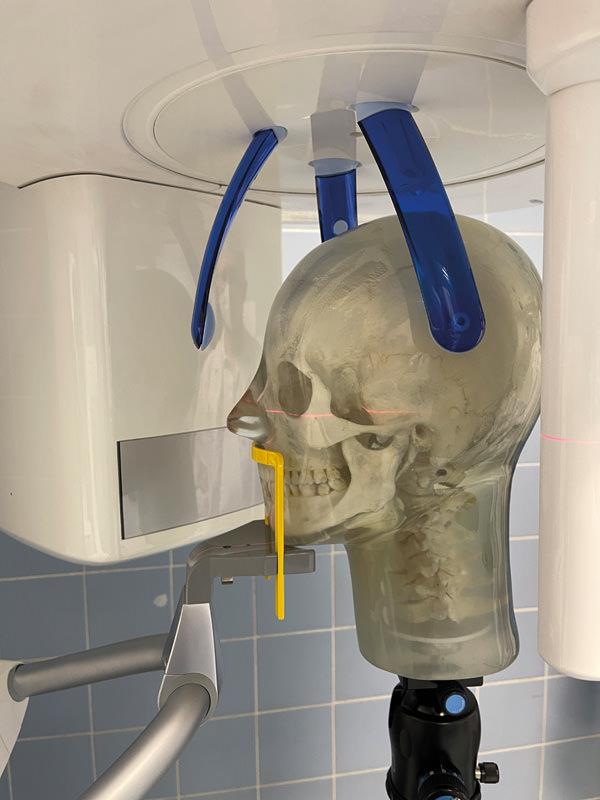

Menschlicher Schädel, sicher eingebettet in Kunststoff für einfache Handhabung. Der Kiefer ist leicht geöffnet, so dass die Zähne gut für Panoramaaufnahmen im Dentalbereich geeignet sind. Der Hals verfügt über Halswirbel. Ein eingebettetes Gewinde ermöglicht die Befestigung eines Stativs.